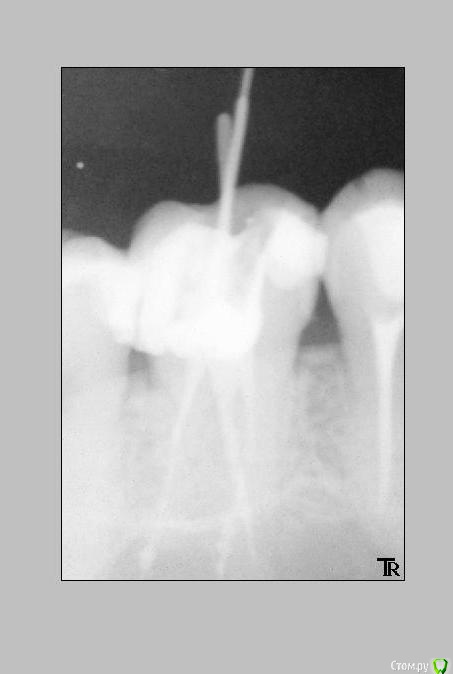

Katya88 Опубликовано 22 декабря, 2014 Поделиться Опубликовано 22 декабря, 2014 Всем здравствуйте. Ситуация такова: заболел зуб справа наверху, болевые ощущения на холодное и горячее, боль при накусывании, к ночи боль усиливалась. У стоматолога сделали снимок, под вопросом были 26 и 27 зуб, снимок этих зубов до лечения №1. В 26 зубе была полость, врач сказал что начнет сверлить, если камера пульповая не вскроется, то удалять ничего не надо, собственно она осталась целой. стоматолога и в 27 кариес, в общем на первом приеме запломбировали оба, стоматолог сказал что если будет ныть то значит в 26 пульпит. Боли не прекратились, а усилились и через неделю мне депульпировали 26 зуб. Сильные боли прекратились, но полностью не исчезли. Через 10 дней боль опять усилилась, и снова появлялась на холодное и горячее, при накусывании и усиливалась к вечеру. Я пошла к стоматологу, путем прикладывания ватки смоченной в горячей воде выяснилось, что болит 27 зуб! И удалили в нем нерв, боли прекратились. Вопросы: мне ошибочно удалили нерв в 26 зубе? Виноват стоматолог? Если пульповая камера целая, то пульпита быть не должно? Как качество запломбированных каналов? Читала что хороший врач на обработку одного канала тратит не менее 30 мин, мой стоматолог три канала обрабатывает за 20 мин))) Мне нужно менять врача? Могло ли быть следующее, сначала пульпит в 26 зубе, а потом в 27? Ссылка на комментарий

Shaid Опубликовано 26 декабря, 2014 Поделиться Опубликовано 26 декабря, 2014 Это может быть либо другой зуб, либо дополнительный(не найденный) канал у леченного зуба. Ссылка на комментарий